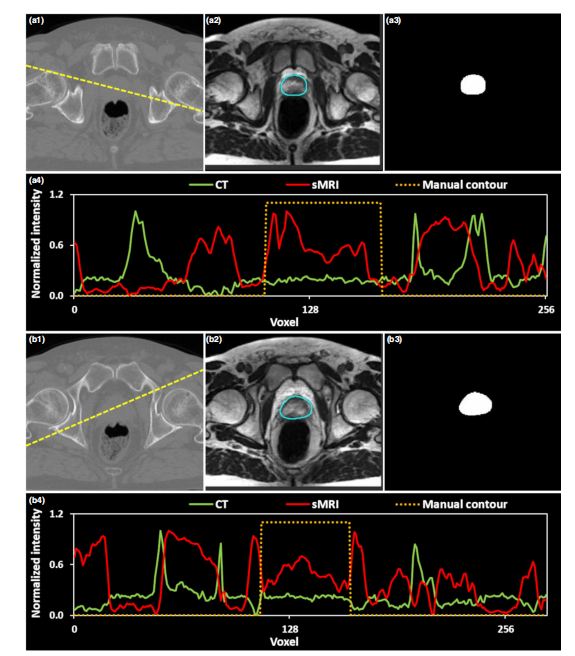

_FIG. 3. 图形展示了生成的人工合成磁共振成像(sMRI)的结果。(a1)和(b1)分别展示了CT图像在两个轴向平面的情况。(a2)和(b2)展示了生成的sMRI图像。(a3)和(b3)展示了发生形变的手动轮廓。(a4)和(b4)详细描绘了CT、sMRI和手动轮廓在黄虚线处的曲线变化情况。

本研究中生成的合成磁共振成像(sMRI)及其视觉结果如图3所示。(a1)-(b1)呈现了两个轴向层面的标准计算机断层扫描(CT)图像。(a2)-(b2)显示对应的生成体素模型sMRI。(a3)-(b3)描绘了手动分割所形成的变形边界。(a4)-(b4)分别展示出(a1)-(b1)中黄线标记区域对应的CT、sMRI以及手动分割解剖学边缘分布情况。